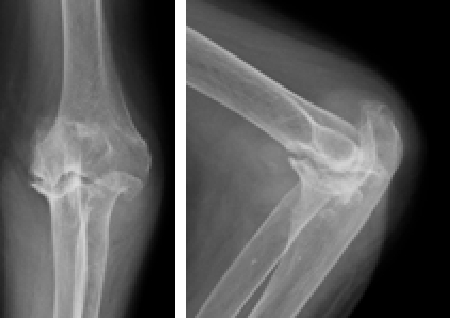

人工関節置換術

関節リウマチや変形性関節症の患者さんで、関節が破壊され機能が失われた症例に対し各関節(指、肘、肩)の人工関節置換術を行ない、関節機能の再建を行っています。

術前

左肘関節の変形を認めます

術後

人工関節して痛みや可動域が改善しました